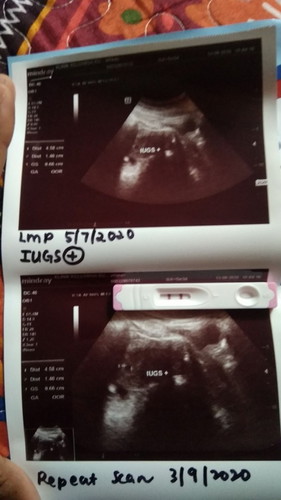

Saya nak mintak semua doakan kandungan saya membesar dengan sihat. Alhamdulillah baru 4week๐

4week scan boleh nmpk bby dh kh ? sy 4 week blm scn lg